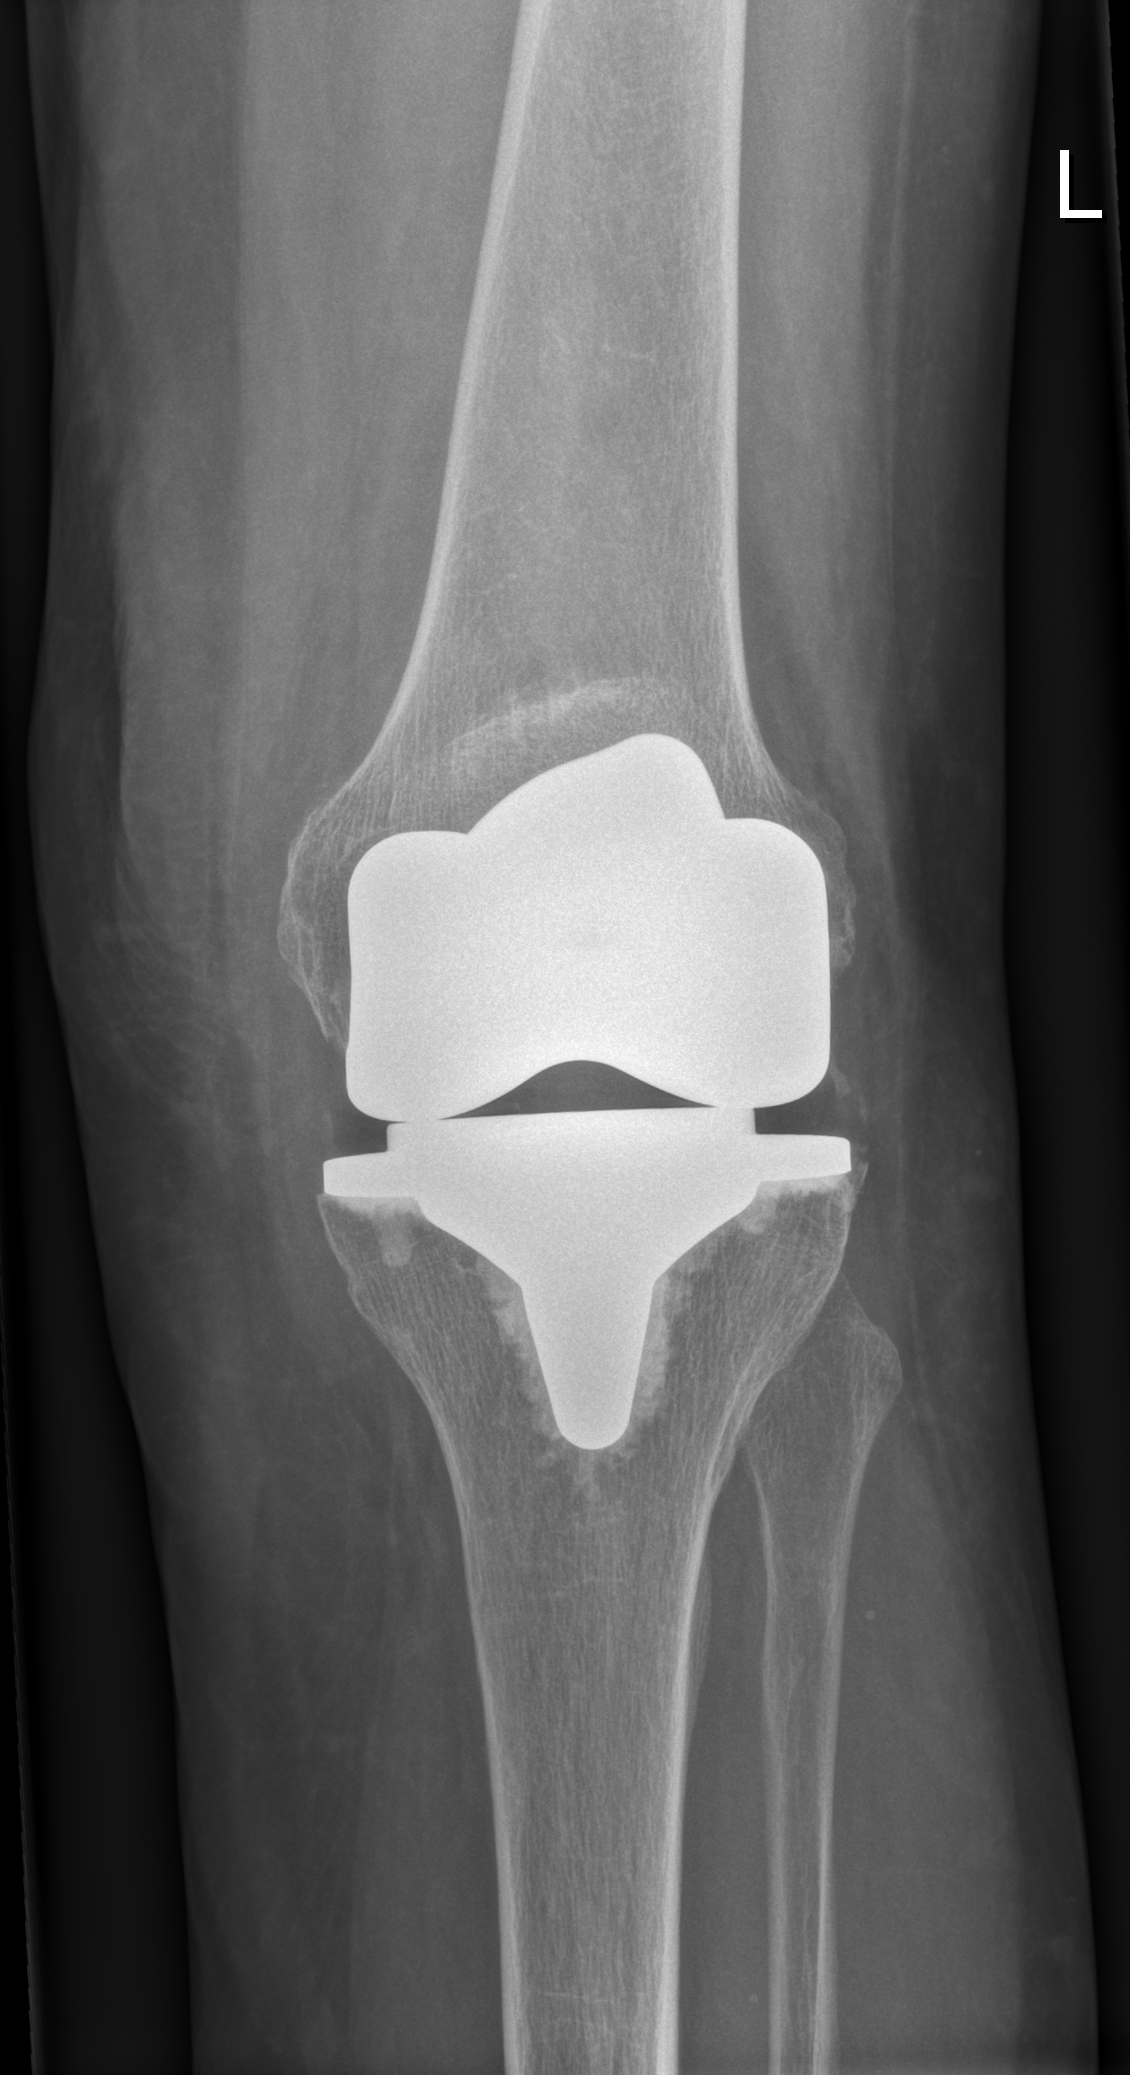

Bei schweren Schäden in mehreren Gelenksteilen ist eine Knie-Totalendoprothese (Knie-TEP) sinnvoll. Dabei werden die Gelenkoberflächen durch Metall ersetzt. Die Kniescheibe muss nur ersetzt werden, wenn diese auch Veränderungen (Knorpelschäden) zeigt.

Knie-Totalendoprothese im Röntgen